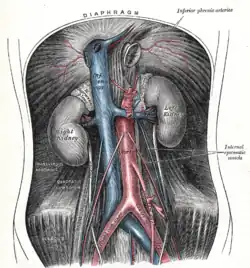

- Bauchaorta (Aorta abdominalis), die sich anhand des Abgangs der beiden Nierenarterien (Arteriae renales) wiederum in zwei Segmente unterteilen lässt:

- Bauchaorta oberhalb der Nierenarterien (Aorta abdominalis suprarenalis), die sofort nach Zwerchfelldurchtritt den Truncus coeliacus zur Versorgung von Magen, Milz, Zwölffingerdarm, Bauchspeicheldrüse und Leber abgibt. Ein weiterer Abgang (Arteria mesenterica superior) versorgt den Hauptteil des Darms und der übrigen Verdauungsorgane.

- Bauchaorta unterhalb der Nierenarterien (Aorta abdominalis infrarenalis), aus der Gefäße für die unteren Darmabschnitte (Arteria mesenterica inferior), den Enddarm und einige Beckenorgane abgehen. Dieser Aortenabschnitt teilt sich schließlich auf Höhe des vierten Lendenwirbels im Becken in die beiden großen Beckenschlagadern (Arteriae iliacae communes) auf.